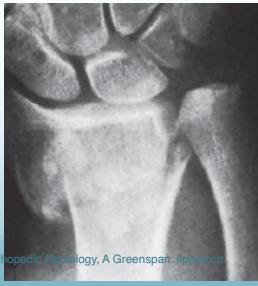

Common Fracture Sites â

- Colleâs fracture (distal radius)